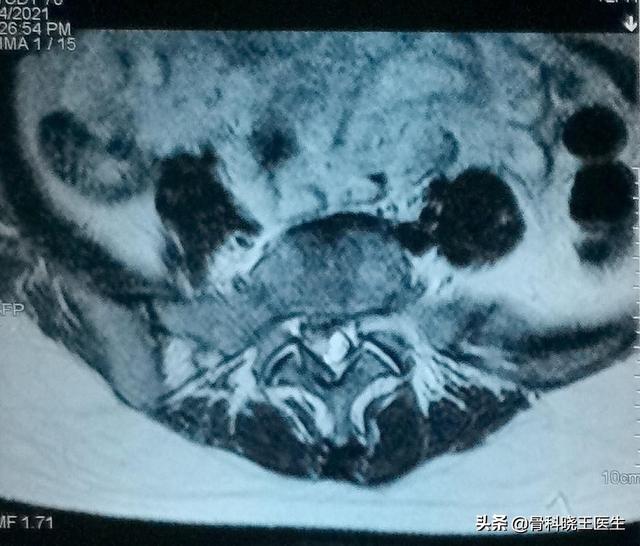

軽度から中等度の椎間板ヘルニアは非常に回復しやすいのですが、重度のヘルニアになると、椎間板の中心にある髄核が後縁の線維性環状組織や後縦靭帯までも突き破ってしまうため、時間の経過とともに回復するのが非常に難しくなります。下は重度の椎間板ヘルニアの患者のCT画像です: